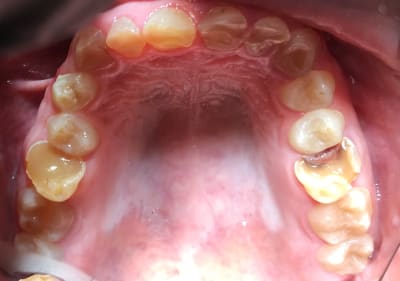

Bonjour je suis lenovo ici . Quelqu’un pourrait-il me donner toutes les étapes pour faire ce cas ? Que faut-il faire précisément ? Le patient n’a pas de contraintes financières. Pas de lésions apicales. Uniquement des usures de dents.

la photo peut tromper mais il semble être en clII,2 en plus.

Je que je trouve impressionnant et peut être le plus complexe à gérer c'est cette bascule du pré maxillaire.

Les photos ne sont pas dingues, mais les usures semblent très majoritairement antérieures. Pourquoi?

Je suspecte un cas d'ortho non traité sous jacent XXL ... que j'aimerais voir sa télé de profil ...

Une ddd par microdontie avec beance et il ont voulu resserrer en voulant reculer le bloc ant mais caramba au lieu de le reculer , il l ont descendu .

Ou alors la trentaine avec handicap , ou malformation , genre bec de lievre .

Dentinogenèse imparfaite + bruxisme